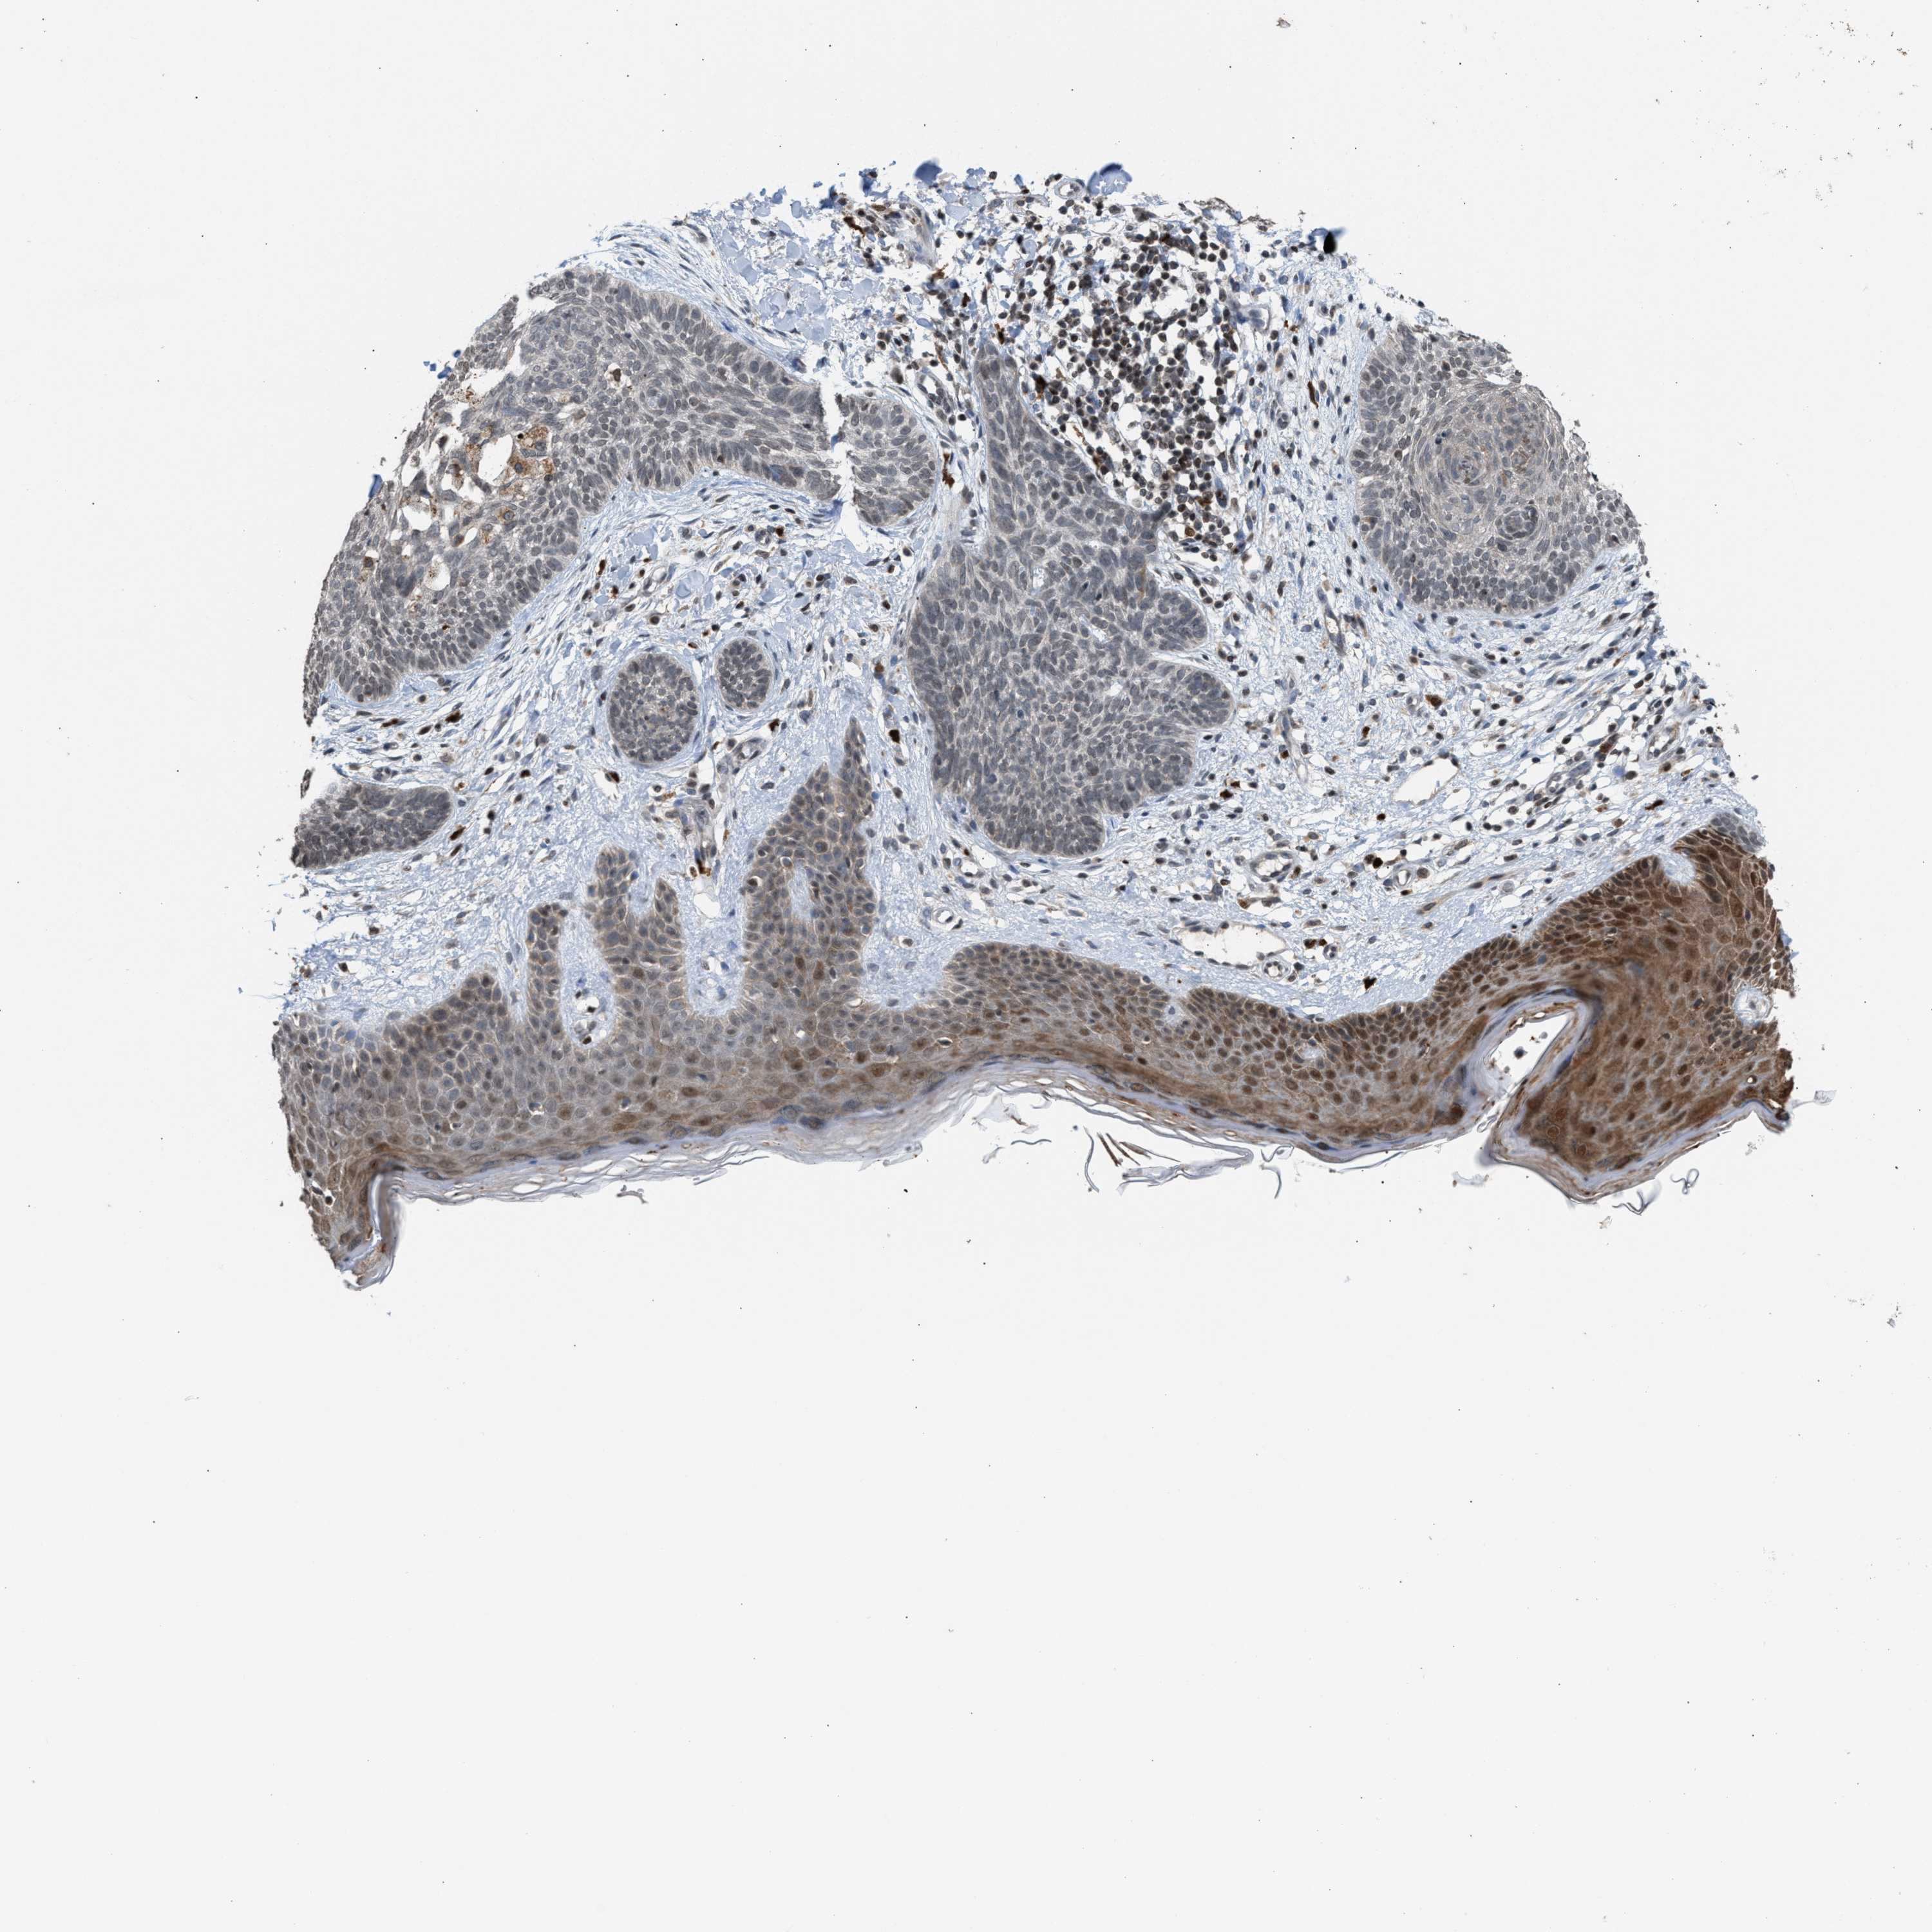

SKIN CANCER - Protein expressioni

A mouse-over function shows sample information and annotation data. Click on an image to view it in a full screen mode. Samples can be filtered based on level of antibody staining by selecting one or several of the following categories: high, medium, low and not detected. The assay and annotation is described here.

Each image is clickable and will lead to virtual microscopy that enables deeper exploration of all samples and also displays staining intensity scores, fraction scores and subcellular localization as well as patient and tissue information for each sample.

Antibody HPA022470

Staining

High

Medium

Low

Not detected

Intensity

Strong

Moderate

Weak

Negative

Quantity

>75%

75%-25%

<25%

None

Location

Nuclear

Cytoplasmic/membranous

Cytoplasmic/membranous,nuclear

Squamous cell carcinoma, metastatic, NOS

Squamous cell carcinoma, NOS